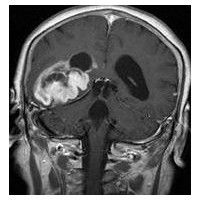

腦部CT圖片最常見的腦瘤是膠質瘤(glioma),其源自膠細胞,而膠細胞是腦組織中的支持性組織。其分類為:

腦癌病變圖雖然沒有特定的臨床症狀可以直接判定惡性腦腫瘤的發生,但局部神經症狀例如顱內壓的產生和加重時則須相當注意,或是沒有癲癇病史的患者有突發性癲癇發作時有可能是由於腫瘤內的出血、腦水腫或腦脊液阻塞所引起,亦應提高警戒。

影像診斷在惡性腦腫瘤的判讀上是相當重要的。

影像檢查:除了臨床症狀的判斷,隨著科學的進步,影像檢查可快速並增加惡收腦瘤診斷的準確性,對於術後追蹤治療也相當有幫助。目前影像檢查包括有:

(1)電腦斷層掃瞄(ComputedTomography;CT);

(2)核磁共振攝影(MagneticResonanceImaging;MRI);

(3)腦波圖(Electroncephalography;EEG)以及腦血管攝影。